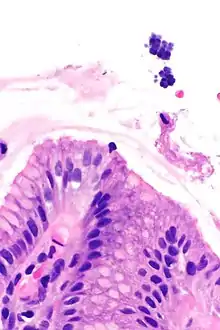

| Gastric mucosa and Sarcina on upper right. H&E stain. | |

Sarcina is a genus of Gram-positive cocci bacteria in the family Clostridiaceae.[2][3][4] A synthesizer of microbial cellulose,[5] various members of the genus are human flora and may be found in the skin [6] and large intestine.[7] The genus takes its name from the Latin word "sarcina," meaning pack or bundle, after the cuboidal (2x2x2) cellular associations they form during division along three planes.[8]